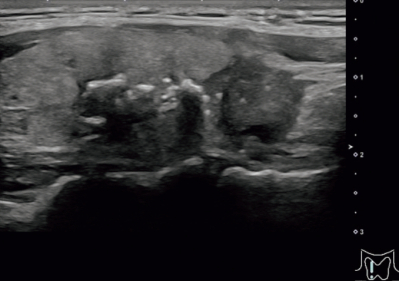

血液所見:赤血球 404 万、Hb 11.6 g/dL、Ht 36 %、白血球 4,800、 血小板 26 万。 血液生化学所見:TSH 0.8 μU/mL(基準0.2~4.0)、FT3 3.1 pg/mL(基準 2.3~4.3)、FT4 1.2 ng/dL(基準 0.8~2.2)、 サイログロブリン 141 ng/mL(基準 5 ~30)。免疫血清学所見:抗サイログロブリン〈TG〉抗体 11.3 U/mL(基準 0.3 以下)、抗甲状腺ペルオキシダーゼ〈TPO〉抗体<0.3 U/mL(基準 0.3 以下)。甲状腺超音波像と頭頸部造影 CTを別に示す。胸部単純 CT で肺野に異常を認めない。甲状腺腫瘤の穿刺吸引細胞診で核溝と核内細胞質封入体を有する異型細胞を認める。